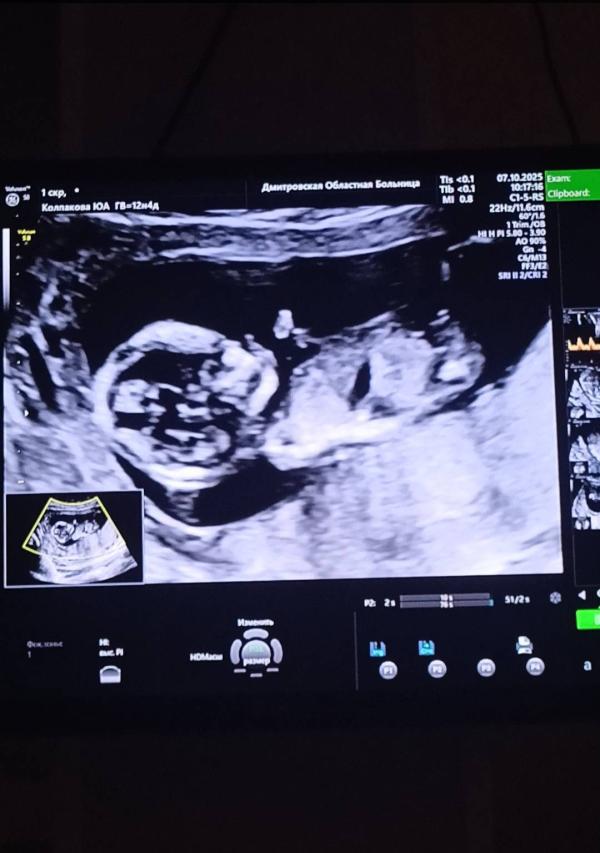

По этой фотке как думаете мальчик ? Или тут непонятно ?

Это фото 12.6 недель (первый скрининг)

Если честно я не вижу тут вообще полового бугорка) фото не удачное наверно) пусть будет тот пол, о котором мечтаете 🙏🤞

А вам узист предположил пол? Мне сказала «думаю что девочка» но я не могла поверить до конца. И в 16 н пошла перепроверять. Тоже сказали девочка

Я вчера попросила написать в конверт, а она сказала я неуверенна и писать не буду ) сказала видит на 80%

@juliakos22 помню с пацанами. Вверх торчал половой богуруг. Я предполагаю что девочка.

@juliakos22 нууу нет , совсем по разному, тут прям вверх, а на снимке в посте лежит

Не вижу полового бугорка